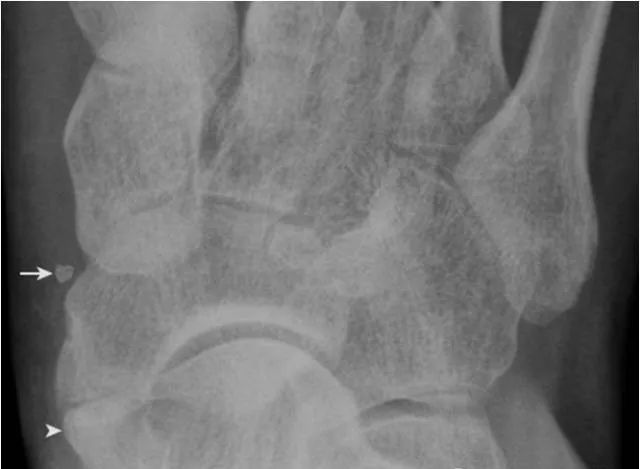

7.跟骨副骨:

位于距骨、跟骨、舟骨及骰骨所围成的间隙内,呈小的骨性突起(箭头),为正常变异。需与跟骨前缘的撕脱骨折鉴别。CT 矢状面重建图像清晰显示该副骨与各骨的关系。